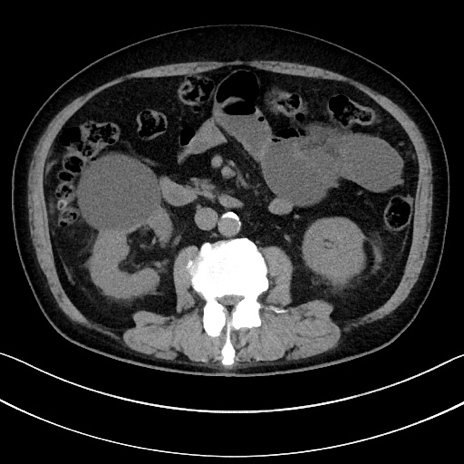

冠状断像

【症例】70歳代男性

【主訴】腹痛

【現病歴】今朝から腹痛あり。全体的に痛い。特に左上の方。排ガスが今日はない。冷や汗が出る。

【既往歴】直腸癌術後

【身体所見】左側腹部〜上腹部に圧痛あり。腹膜刺激症状明らかなではない。軽度反跳痛。左下腹部に術後瘢痕あり。

【データ】WBC 7700、CRP 0.02